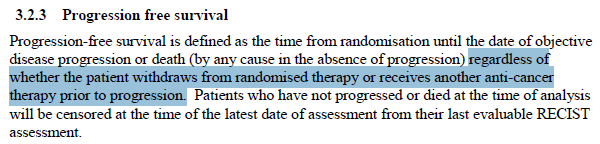

еңЁAENEASе’ҢFURLONGдёӯ����пјҢе…ідәҺеёҢжңӣеүҚжҺҘеҸ—NACTзҡ„жӮЈиҖ…����пјҢеңЁдё»иҰҒеү–жһҗдёӯеқҮе°ҶPFSеҲ еӨұеҲ°жңҖе…ҲNACTеүҚзҡ„жң«ж¬ЎеҪұеғҸеӯҰжЈҖжҹҘж—ҘжңҹпјҲеӣҫ8пјү��гҖӮ

еҮӯиҜҒICH E9пјҲR1пјү[18]����пјҢжӮЈиҖ…еёҢжңӣеүҚжҺҘеҸ—NACTеұһдәҺдјҙеҸ‘дәӢеҠЎзҡ„дёҖз§Қ����пјҢеҸҜдҪҝз”Ёз–—жі•жҲҳз•ҘжҲ–и®ҫжғіжҲҳз•ҘжқҘи§ЈеҶіпјҡз–—жі•жҲҳз•ҘдёӢдјҙеҸ‘дәӢеҠЎзҡ„зҲҶеҸ‘дёҺз•ҢиҜҙжІ»з–—ж•Ҳеә”ж— е…і����пјҢеҚіж— и®әжҳҜеҗҰзҲҶеҸ‘дјҙеҸ‘дәӢеҠЎ����пјҢеқҮдјҡдҪҝз”Ёзӣёе…іеҸҳйҮҸзҡ„еҖј����пјҢFLAURA继з»ӯдҪҝз”ЁNACTеҗҺзҡ„еҪұеғҸеӯҰж•°жҚ®����пјҢеҚідёәз–—жі•жҲҳз•Ҙ��пјӣи®ҫжғіжҲҳз•ҘеҲҷи®ҫжғідёҖз§ҚжІЎжңүзҲҶеҸ‘дјҙеҸ‘дәӢеҠЎзҡ„жғ…жҷҜ����пјҢдҪ“зҺ°дёҙеәҠй—®йўҳзҡ„еҸҳйҮҸеҖјжҳҜеңЁжүҖеҒҮи®ҫзҡ„жғ…жҷҜдёӢжҺҘзәізҡ„еҸҳйҮҸеҖј����пјҢAENEASе’ҢFURLONGдёӯе°ҶNACTеҗҺзҡ„еҪұеғҸеӯҰж•°жҚ®дҪңеҲ еӨұеӨ„зҪ®жғ©зҪҡ����пјҢеҚідёәи®ҫжғіжҲҳз•Ҙ��гҖӮ